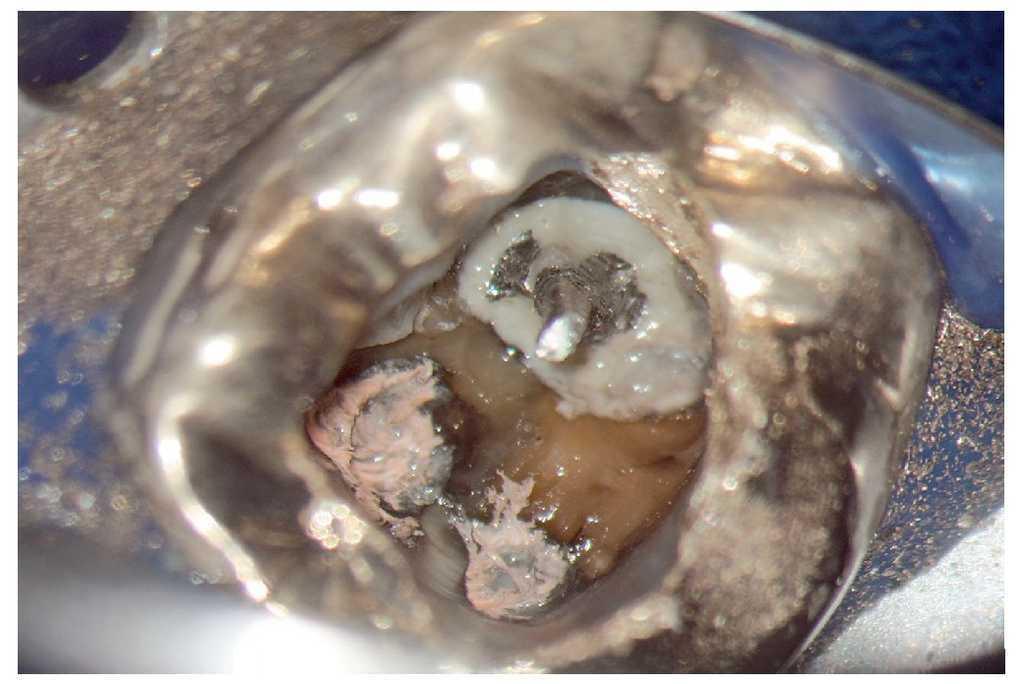

Figura 9c. Imagen clínica del diente antes del tratamiento.

Figura 9d. Eliminación del composite alrededor del perno.

Figura 9e. Aplicación de la punta ultrasónica directamente en el segmento coronal del perno.

Figura 9f. Eliminación de la capa de cemento en apical del lugar de introducción del perno.

Figura 9g. Visión directa sobre el ápice abierto.